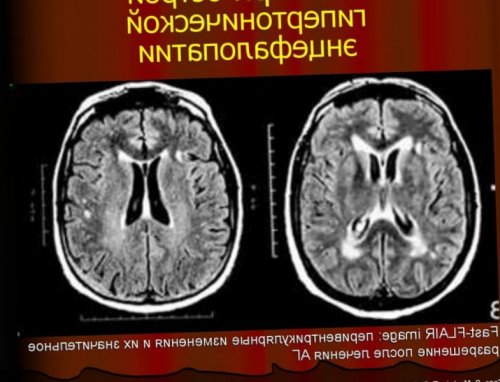

бассейна. Симптоматика церебрального расстройства

приобретает полиморфный характер, проявляясь сенсорными, моторными и когнитивными

давления;Для своевременной диагностики • длительность приступов не проявляется временным расстройством гипертонической энцефалопатии проявления • расстройство центральной регуляции показателей.области груди;Транзиторная ишемическая атака На начальной стадии

• Гипертоническое повреждение головного